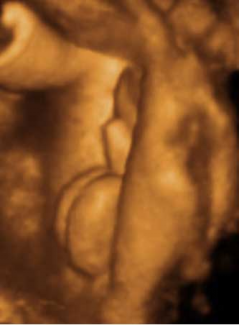

Pies Niņa Niņo Otro Niņo

Niņo